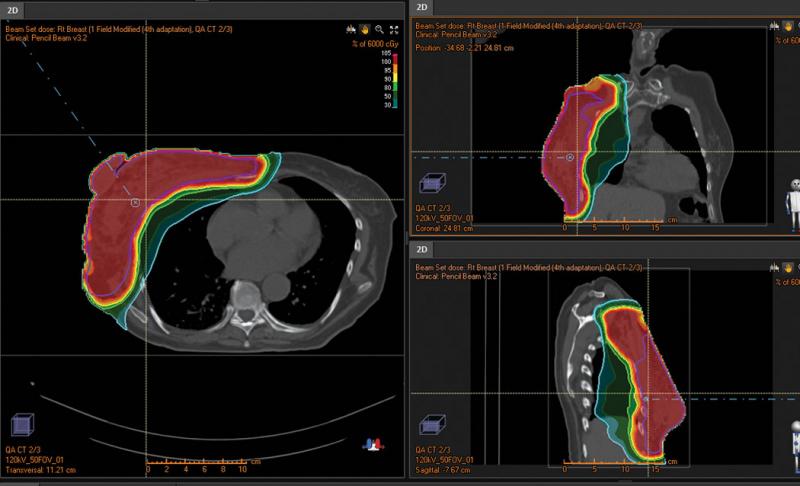

The first example demonstrates how important it can be to modify plans based on changes during treatment. A woman presented with a right breast cancer that was very large and invasive. It was expected that the patient would have a fast response so weekly QA CTs were performed during treatment. Deformable registration was used to determine if the existing plan had adequate coverage. Soon after the treatment commenced, the scans showed significant changes that warranted replanning. The center used the adaptive planning function in RayStation to quickly replan the case and get back to the prescribed dose. The adaptive planning function does not require that the user re-enter the beam parameters or the inverse planning objectives. In total four adapted plans were implemented over the course of treatment with only a day or so needed each time to complete the planning and quality assurance. The sum of the doses was easily displayed so that an overall analysis could be made on the efficacy of the delivery. Adaptive planning in a case like this is simply unavoidable - in the case of protons that are sensitive to density and anatomical changes in the body, it would be impossible to plan this in an efficient and/or safe manner without advanced technologies such as deformable registration and adaptive therapy.